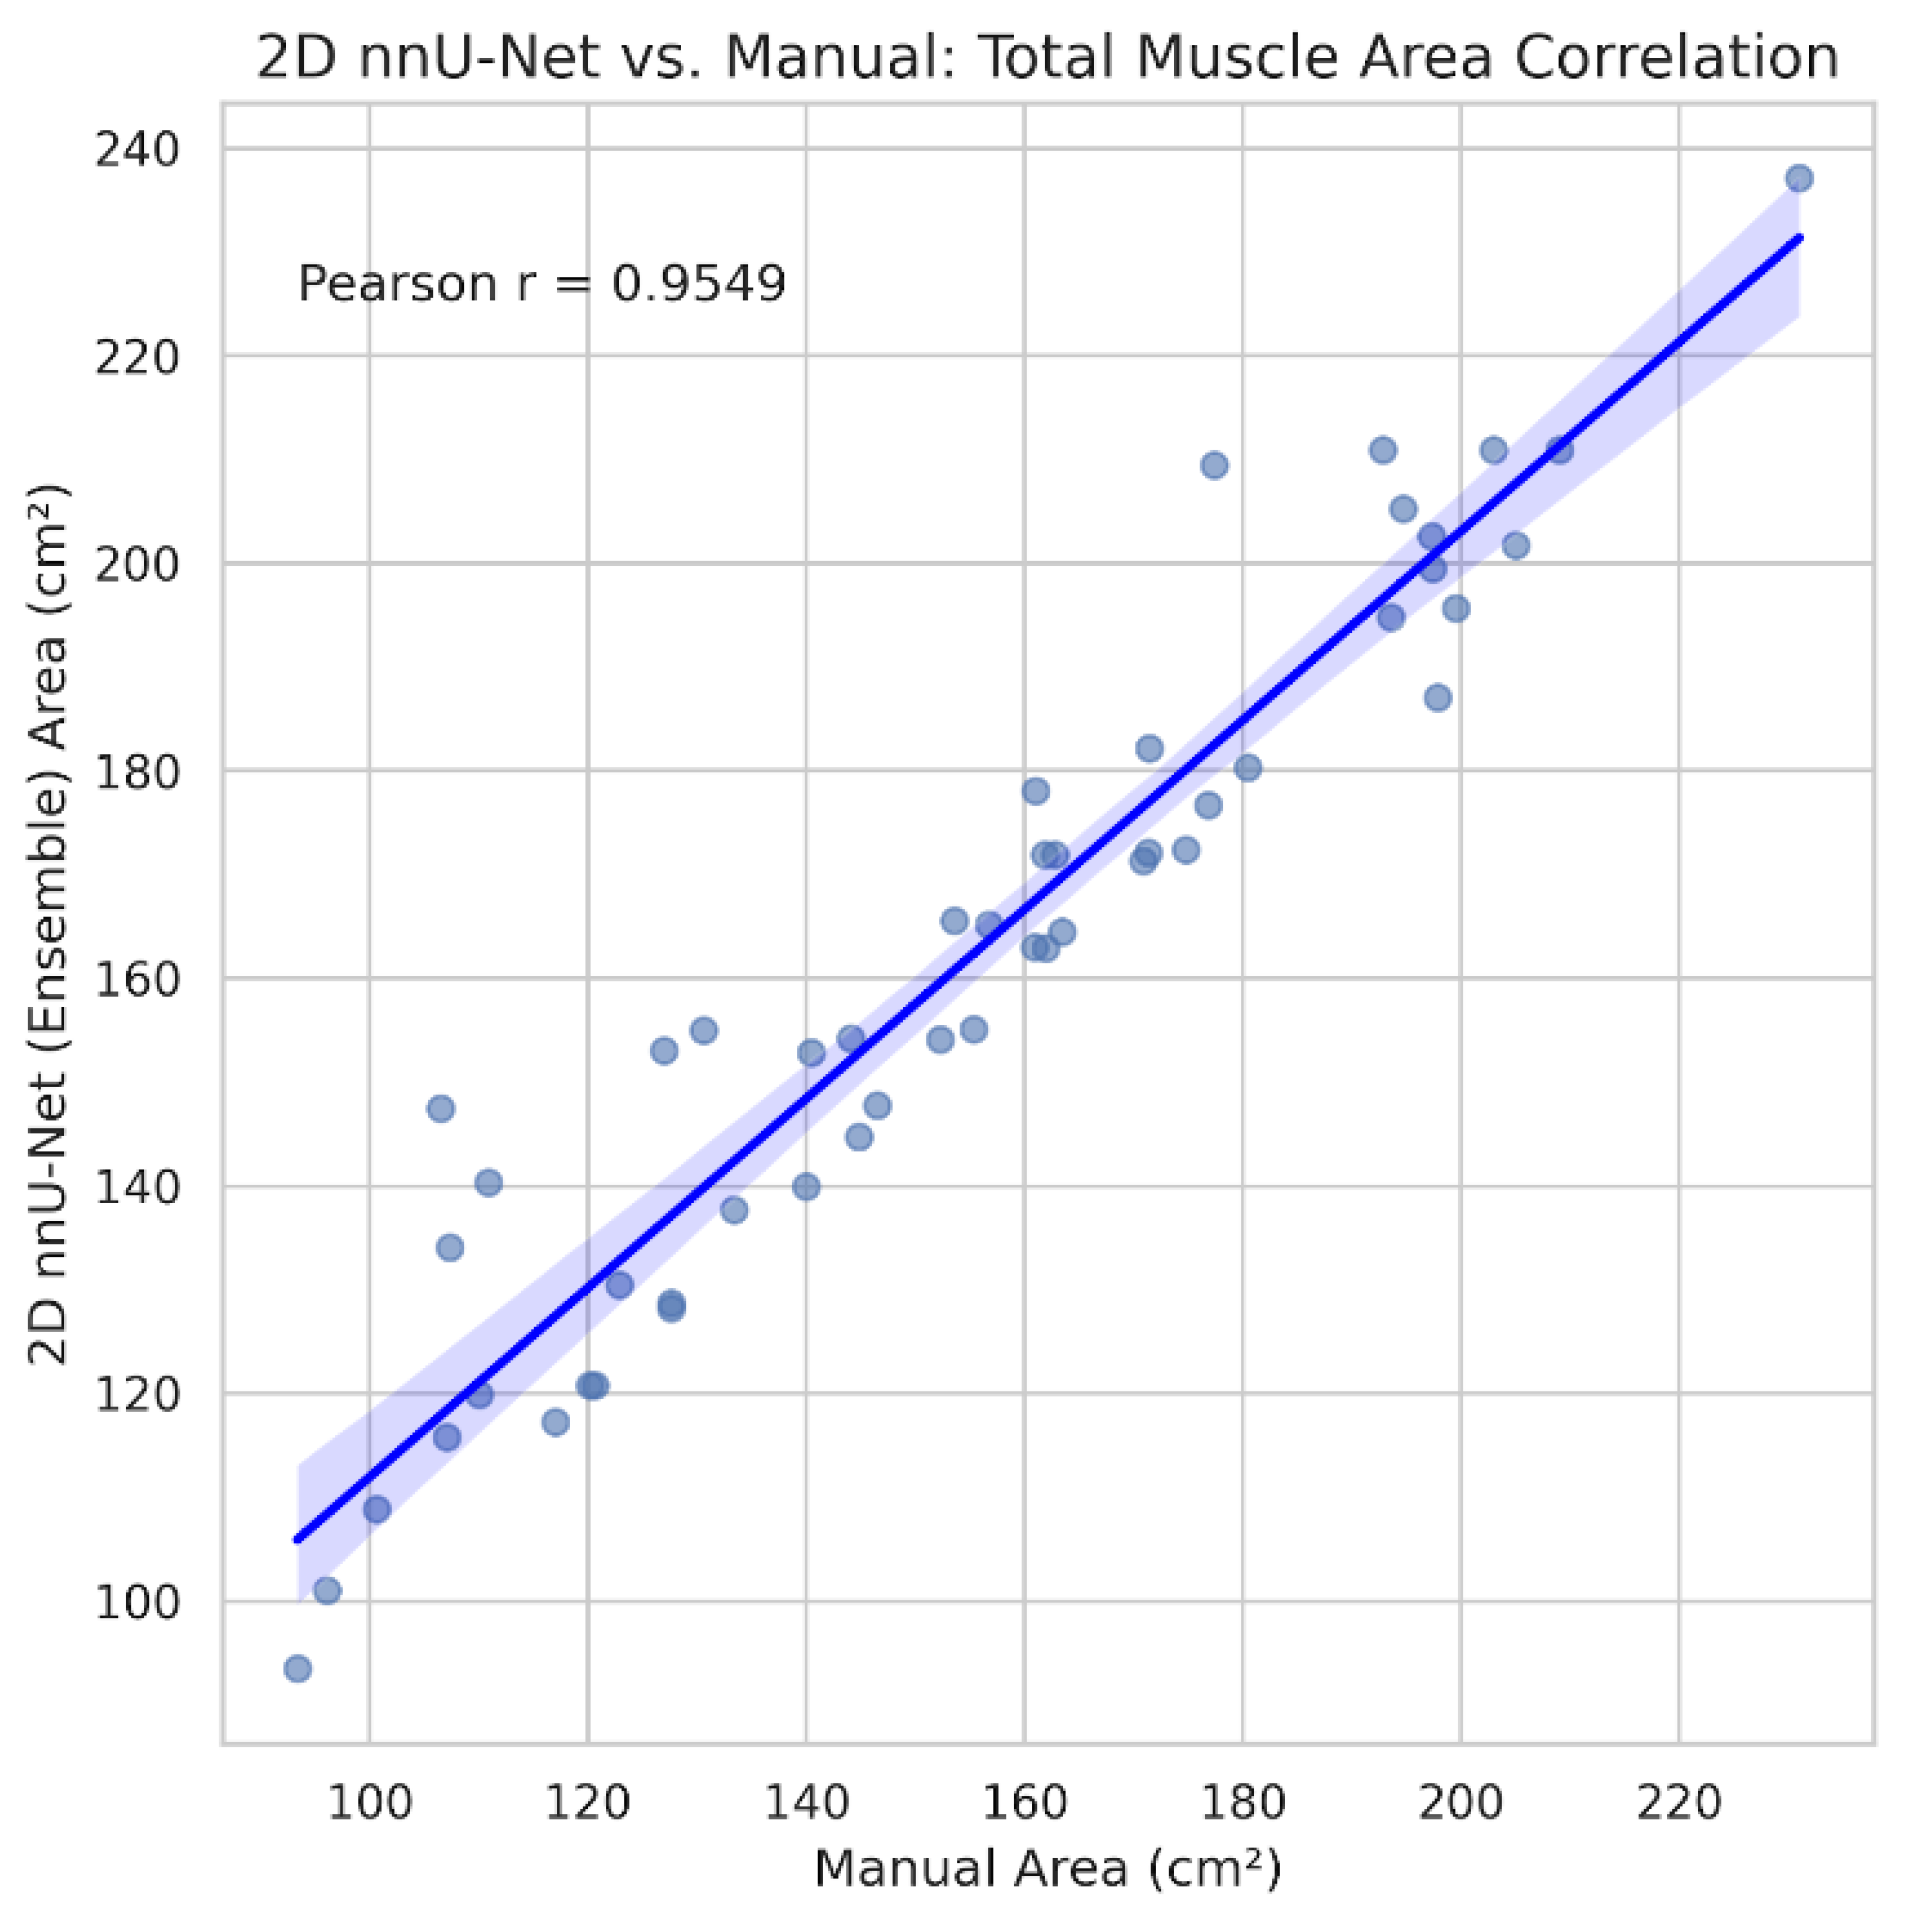

3.3. Clinical Agreement and Bias Analysis

| Metric | Pearson r | MAE | Mean bias (nnU-Net - manual) |

|---|---|---|---|

| Total muscle area (cm²) | 0.955 | 8.00 | +7.17 |

| Total mean attenuation (HU) | 0.968 | 2.33 | -1.67 |